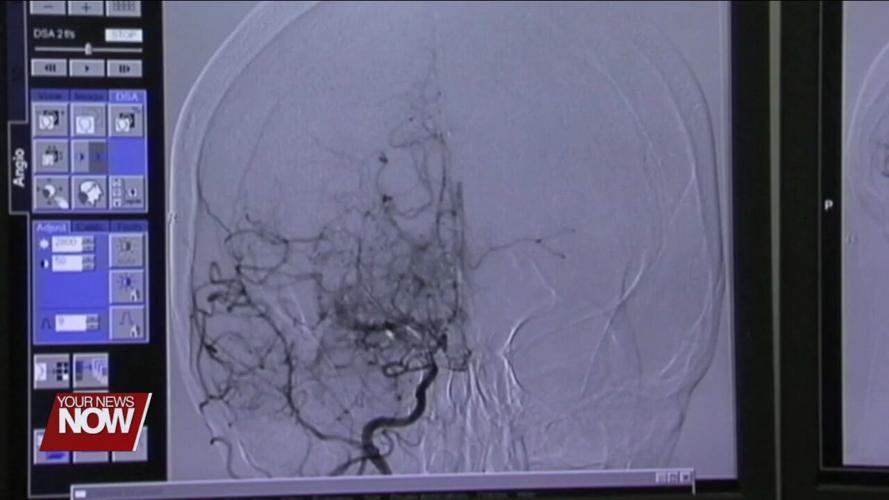

LIMA, OH (WLIO) - It is the lack of blood to the brain that can cause mild to moderate damage and even death if not addressed immediately.

May is Stroke Awareness Month, and local health officials want people to recognize the causes and symptoms of stroke. High blood pressure is at the top of the list as a cause of strokes. Warning signs and symptoms include loss of balance, speech difficulty, and facial drooping. It is crucial to get medical attention if you suspect a stroke.